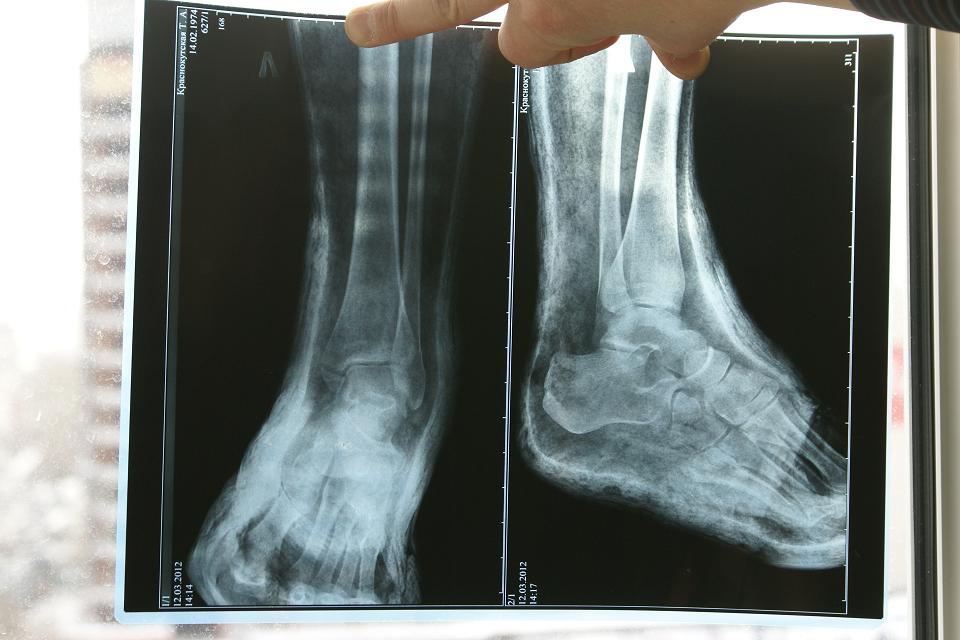

Двулодыжечный перелом со смещением и подвывихом кнаружи.

Через 4 часа после перелома была сделана репозиция и наложен циркулярный гипс. Сегодня 10 дней со дня репозиции, опухоль спала, гипс болтается, натерла мозоль под гипсом. Надо ли перекладывать гипс, или терпеть и ждать 21 день (как говорит лечащий доктор). И еще - на снимке идеально поставили внешнюю лодыжку, а у внутренней отломан нижний край и на снимке расстояние между обломками где то 1 мм, нужно ли делать штырь или есть шанс, что все и так срастется? Снимок прилагаю